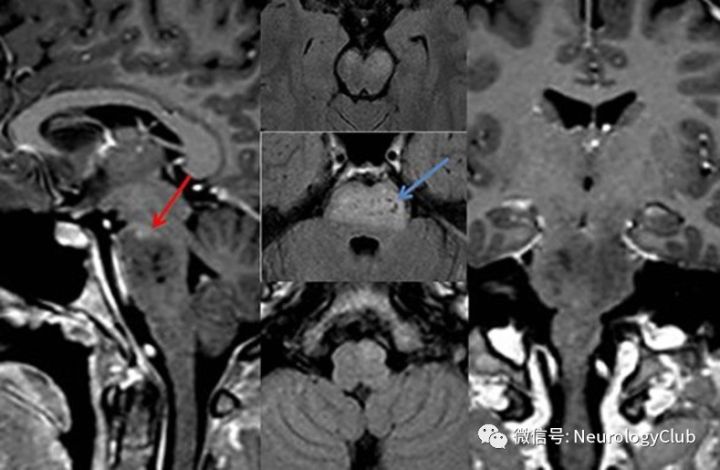

(图20:矢状位[左]和冠状位[右]增强T1可见位于双侧大脑脚和腹侧脑桥的广泛低信号病灶伴脑桥顶部轻度强化;FLAIR[中]可见大脑脚和脑桥腹侧高信号病灶伴囊性变,左侧下橄榄核高信号,提示肥大性下橄榄核变性)